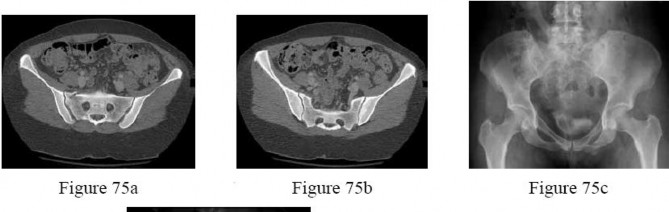

- are the CT scans and radiographs of a 56-year-old man who is a restrained driver involved in a motor vehicle accident in which his car is struck at 35 mph. He has pain to the right buttock and groin regions. Examination reveals that he is neurologically intact and has no evidence of other injuries. What is the most appropriate management at this time?

Bed rest for 1 to 2 weeks, followed by non-weight-bearing on the right side for 4 weeks

Immediate mobilization and weight bearing as tolerated on the right lower extremity

No detailed explanation provided for this question.